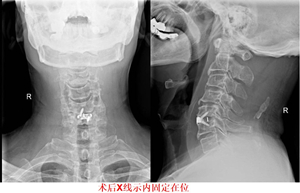

这个病人刚来门诊说他头晕了半年多,最近半个月脖子和肩膀也开始不舒服了。看他走路很僵硬,就简单查了下体,结果右腿肌张力高,右侧上肢病理征阳性,右侧腱反射也增高。再看了看他的检查结果——脊髓型颈椎病!

那这肯定要手术治疗!再跟病人一聊发现这个60多的老爷爷还是越战老兵,那一定得好好整,整的好好地!